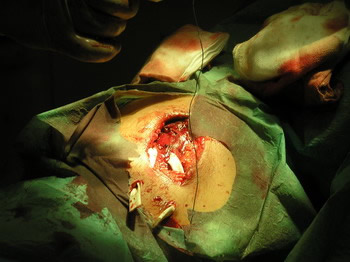

Lesiones: Dos cornadas paralelas a nivel del 1/3 medio cara anterointerna de muslo derecho que afectan a todos los planos de la extremidad y con trayectorias de 20 y 25 cms. de longitud respectivamente. Se interviene en enfermería de la plaza de Toros de Valverde del Camino realizandose cuidadosa exploración de las heridas, desbridamiento, limpieza y drenaje de las mismas.

Diagnóstico: Herida por asta de toro con doble trayectoria en cara anterointerna de 1/3 medio de muslo derecho.